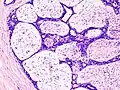

| Histopathologic image of breast fibroadenoma. Core needle biopsy. H&E stain. | |

Fibroadenoma of the breast is a benign tumor composed of a biplastic proliferation of both stromal and epithelial components.[12][13] This biplasia can be arranged in two growth patterns: pericanalicular (stromal proliferation around epithelial structures) and intracanalicular (stromal proliferation compressing the epithelial structures into slit-like spaces).

These tumors characteristically display hypovascular stroma compared to malignant neoplasms.[2][14][9] Furthermore, the epithelial proliferation appears in a single terminal ductal unit and describes duct-like spaces surrounded by a fibroblastic stroma. The basement membrane is intact.[15]

Fibroadenoma histology (H&E). The image demonstrates intracanalicular morphology (bottom left) and pericanalicular morphology (top right) -

Histopathologic image of breast fibroadenoma. Core needle biopsy. Hematoxylin & eosin stain. -

Histopathologic image of breast fibroadenoma showing proliferation of intralobular stroma compressing and distorting the epithelium. H&E stain. -